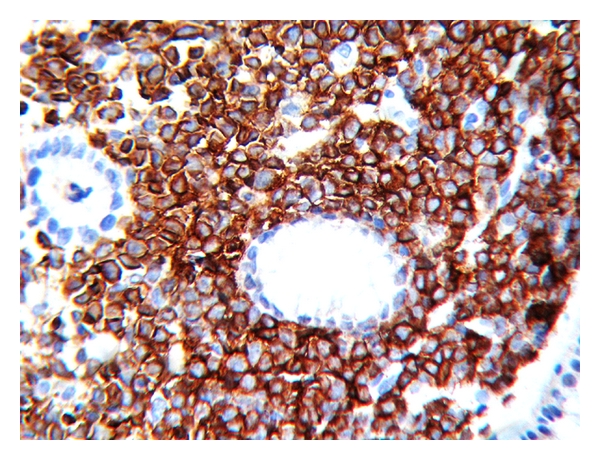

A 25-year-old woman with 17 weeks of gestation (G3P2) presented with progressive dysphagia, epigastric discomfort, persistent postprandial vomiting, and weight loss for one month. Initial investigations were within normal limits. Upper GI endoscopy showed thickened nodular friable mucosa at cardia of stomach extending into the posterior wall (Figure 1). Multiple deep biopsies from gastric cardia showed normal mucosal glands with expansion of lamina propria by infiltrates of atypical cells, intermixed with granulocytic precursor cells (Figure 2). Immunohistochemistry panel showed that the cells were negative for CD20, CD5, CD3, CD10, and cytokeratin markers, with intense positivity for immature myeloid markers (myeloperoxidase, CD34, and CD117) (Figure 3), consistent with granulocytic sarcoma of the stomach. A week later she developed fever with WBC count of 34,800 cells per cu mm. A bone marrow biopsy (Figure 4) and flow cytometry analysis showed features consistent with acute myeloid leukemia (AML-M4) with blast count of 77%. Pregnancy was terminated.